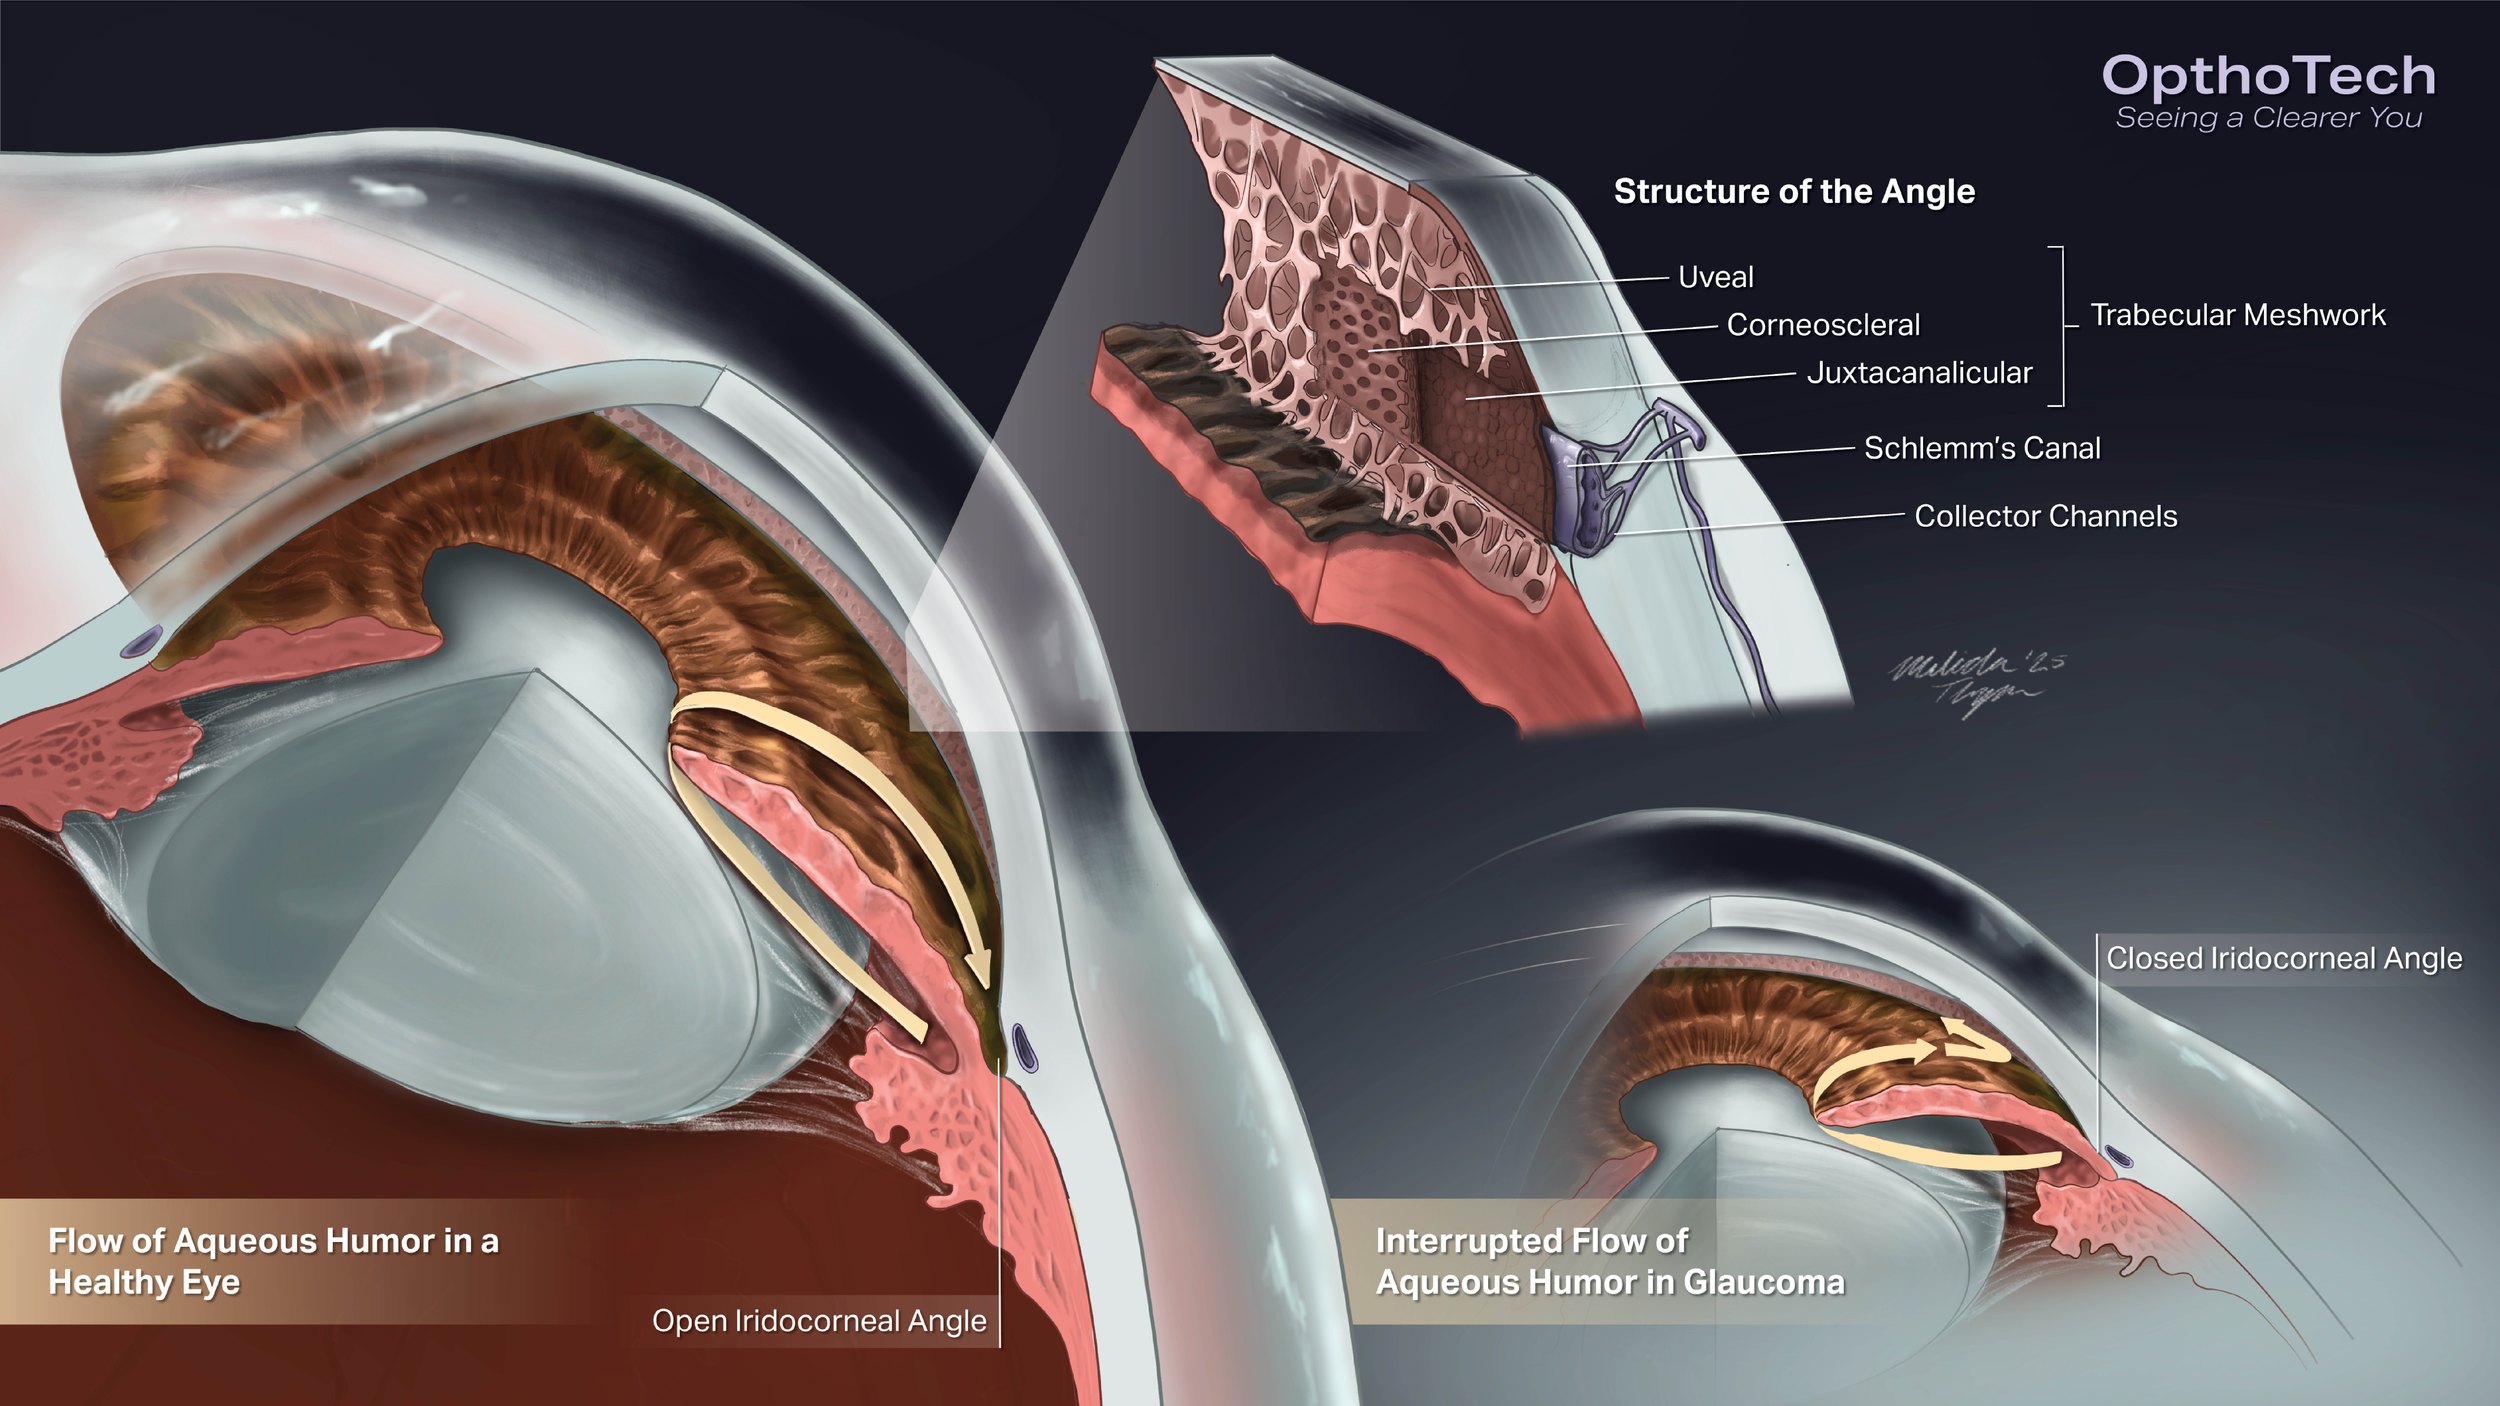

Illustrated Powerpoint Slide: Anatomy of the Iridocorneal Angle